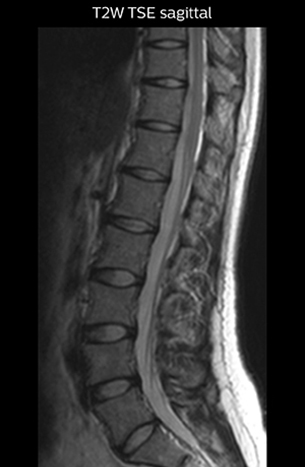

“For example, in sagittal images, when the presence of fat is observed in the intervertebral foramen, it suggests that there is a margin around the nerve. Similarly, the absence of fat indicates that the nerve is being compressed. So, we used to deduce nerve compression indirectly. With NerveVIEW, however, we can observe the condition of the nerves directly, regardless of the presence or absence of fat. We always prefer such direct observation of anatomy over having to make an inference about it.”

“The intra-luminal signal of veins, especially around the intervertebral space, can be suppressed well with NerveVIEW. As a result, we can easily observe the detailed nerve structure around the posterior ganglion,” he says. “This is why we use 3D NerveVIEW for intraforaminal stenosis and extraforaminal stenosis/herniation (lateral disc herniation). On the other hand, if herniation is suspected to exist inside the dorsal root ganglion (DRG), balanced TFE or ProSet-FFE is applied. NerveVIEW is not suitable for evaluating the median type of herniation.” The SE-EPI DWI-based method for MR neurography works well for large FOV exams like whole-body MRI, but focal examination of nerves is often limited by the attainable spatial resolution (both inplane and slice direction) and geometric distortion. “3D NerveVIEW achieves higher in-plane resolution – close to our other routine spine sequences – and the source images can be used instead of adding a fat-suppressed T2-weighted sequence,” Tanji says.